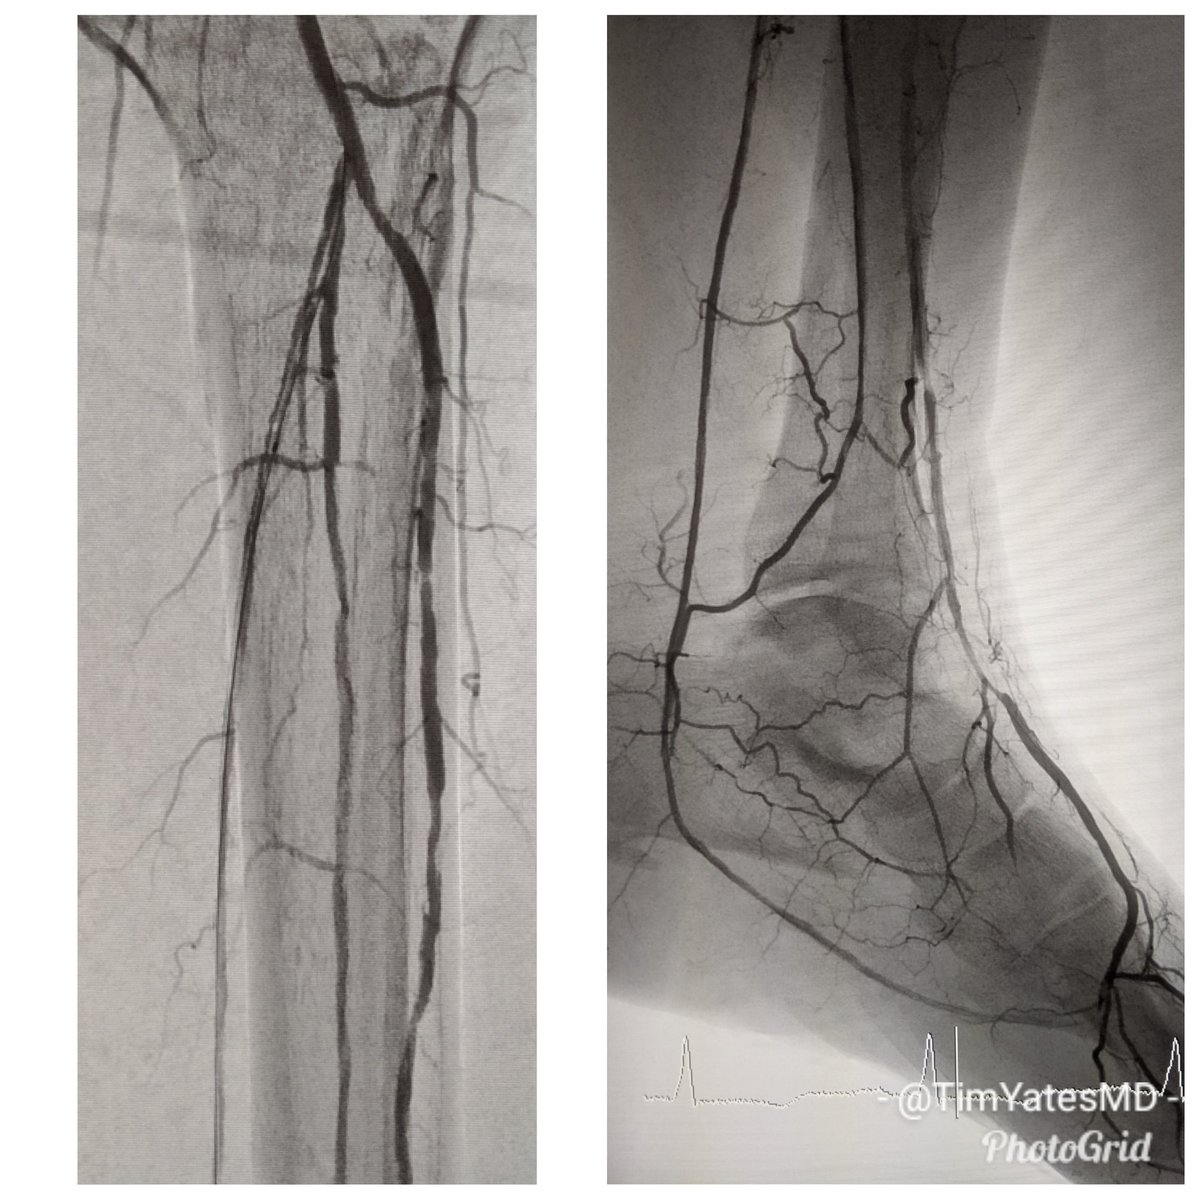

Great day for 3 vessel runoff and a complete pedal plantar loop. RC5 L 2-4 toe #CLI after degloving injury. #CSI @belzerj @AbbottGlobal #commandwire @CLI_Global @CLIfighters #CLIfighters @FadiSaab17 @Mustapja @SIRspecialists @SIRRFS @SIR_ECS @SriniTummala @kmadass @BOlivieriMD